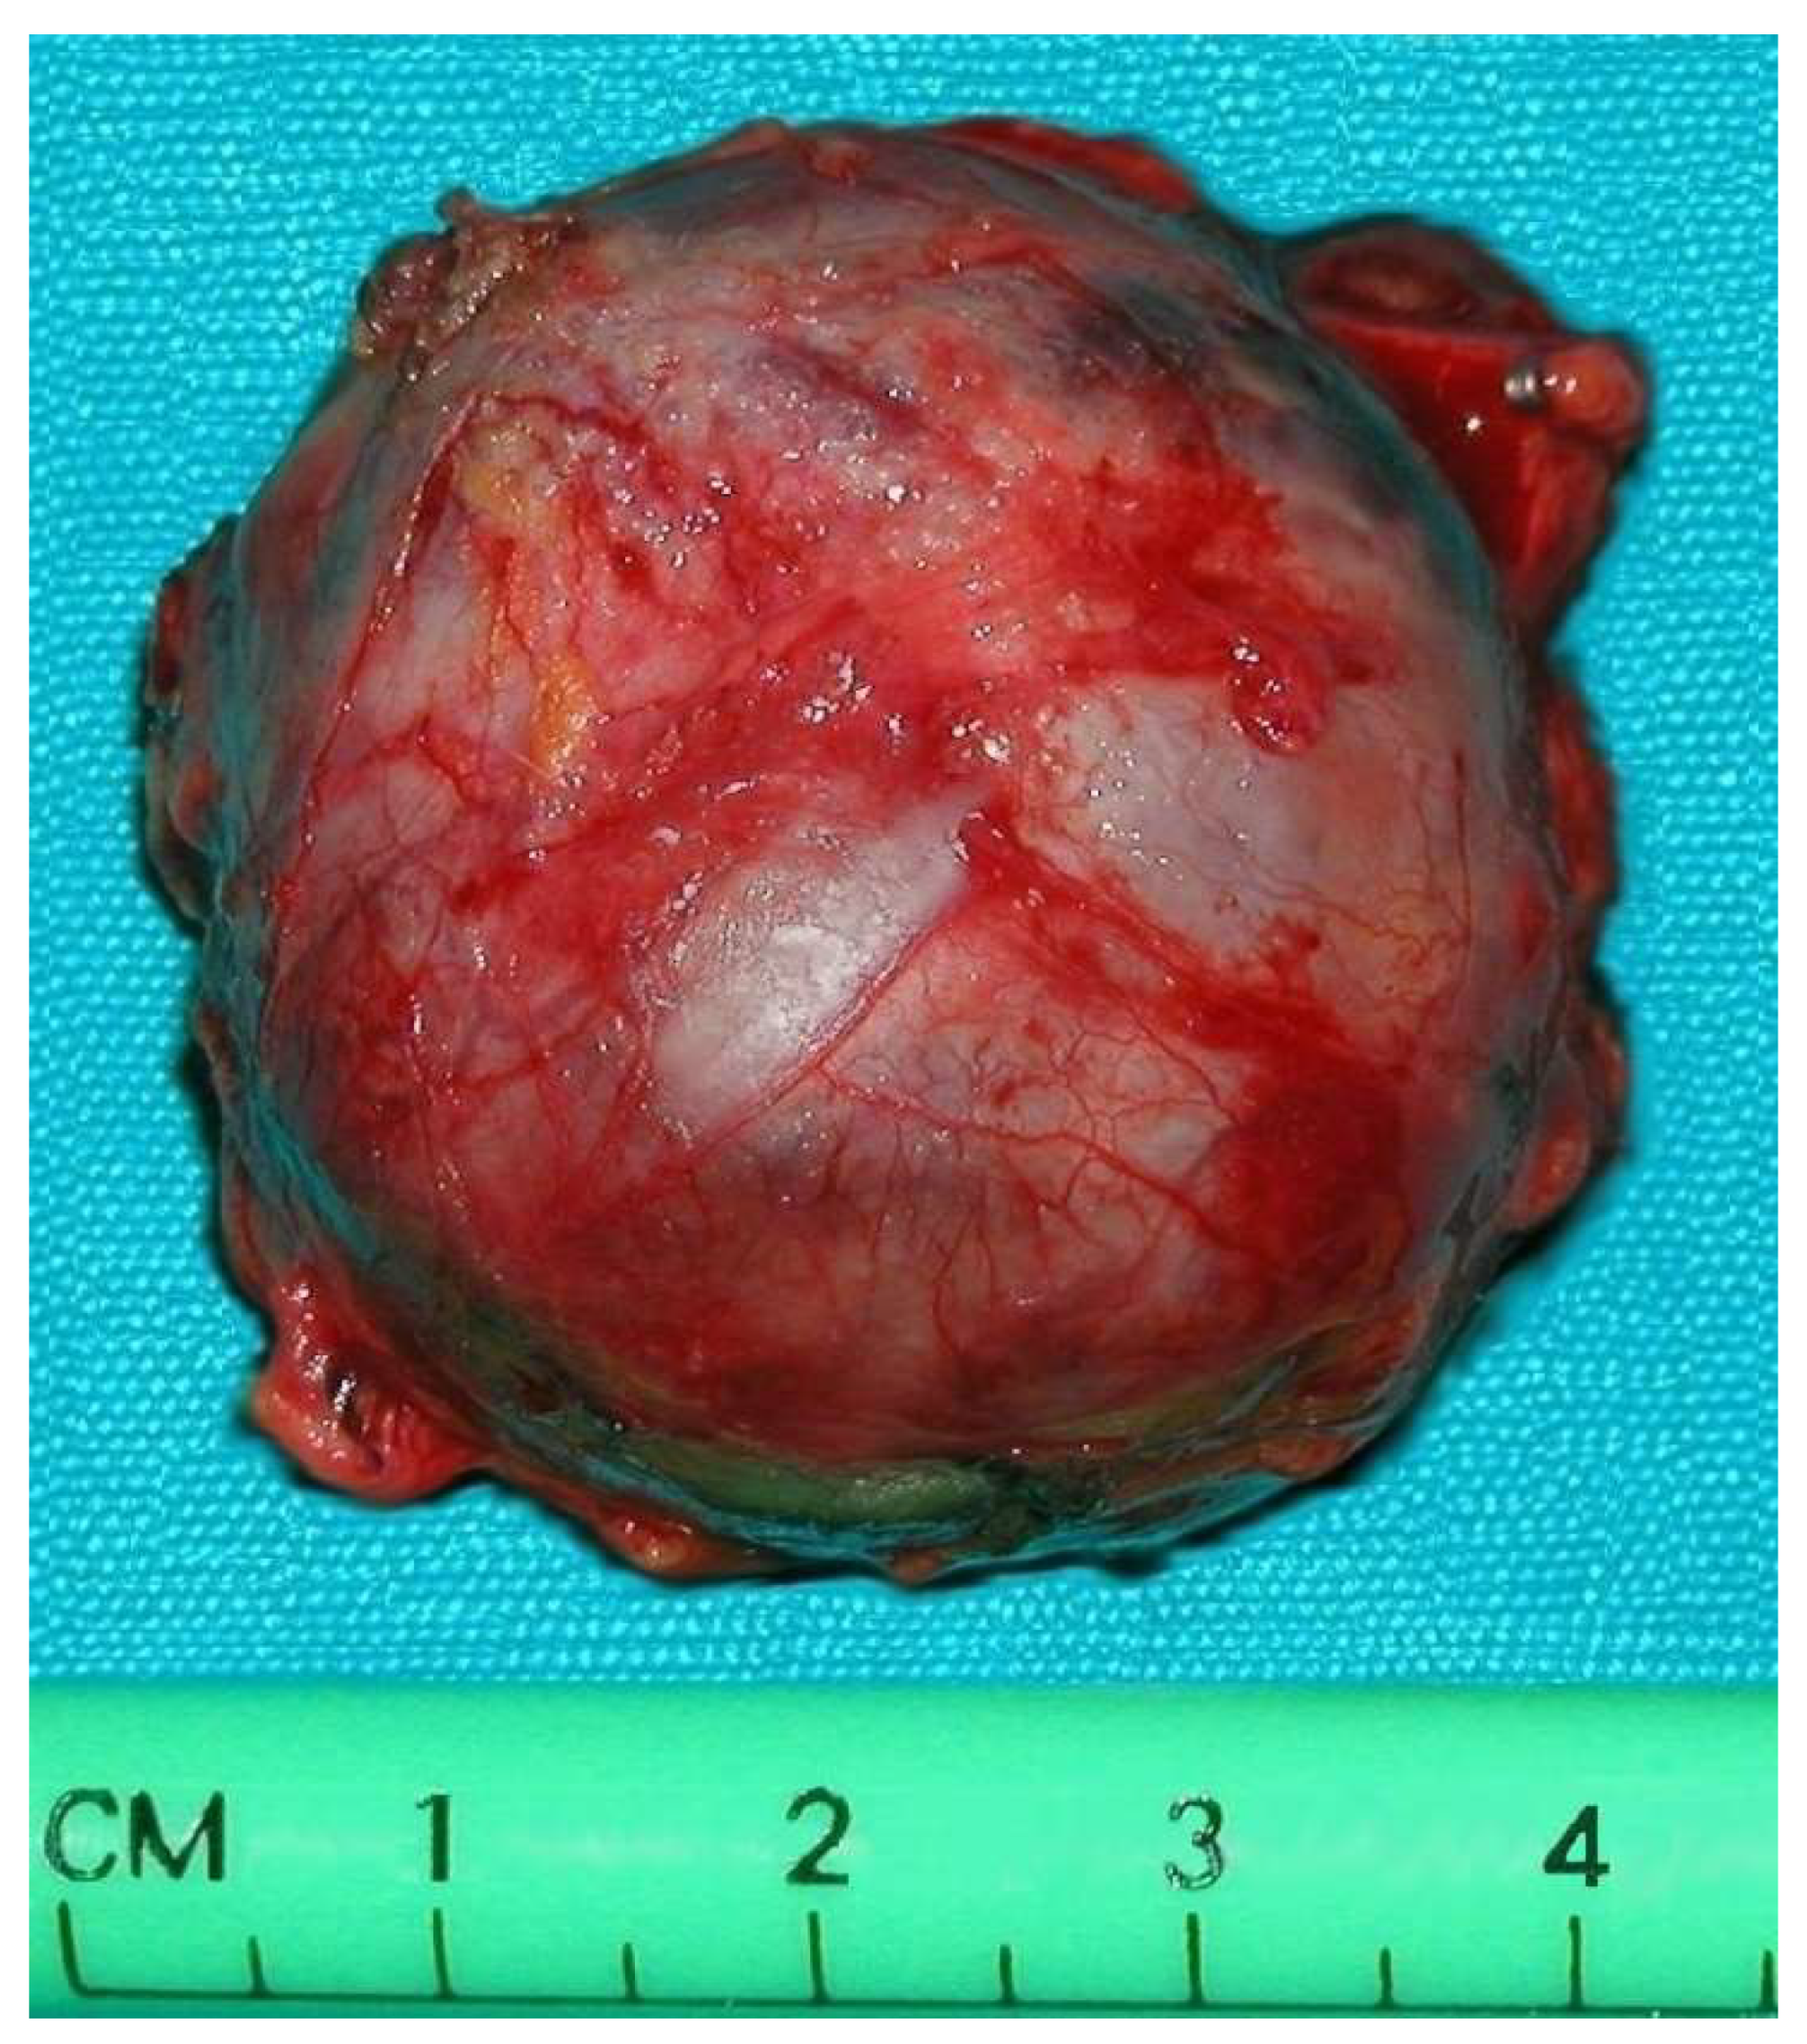

All operations were performed by the same endocrine surgical team. The surgical approaches chosen were laparoscopic excision with transperitoneal approach and abdominal laparotomy based on the results of preoperative investigations considering the position of the mass and the bleeding risk. Laparoscopic approach was performed in four cases (30.7%) and abdominal laparotomy in the other nine (69.3%). Combined abdominal and neck surgery was performed in one case of dual-localization PGL: peri-carotidal and para-aortic. In addition, we performed one left adrenalectomy for the excision of a PGL under the left renal vein using surgical laparotomy, and in another case, cytoreductive surgery was carried out due to the intraoperative discovery of carcinosis (Figure 1 and Figure 2). This patient died eight years later, with massive thorax and abdominal metastases. Another patient died three years after the surgical intervention for malignant hypertension due to metastatic PHEO. The follow-ups for the other 11 patients showed them to be free from disease following operation (follow-up time from 1 year to 10 years).

Figure 1. Adrenal pheochromocytoma (A) and abdominal paraganglioma under the left renal vein (B).

Figure 2. Malignant paraganglioma with peritoneal carcinosis.